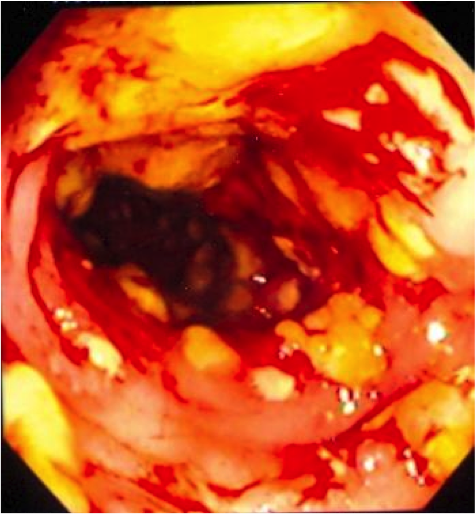

What does Pseudomembranous colitis- C. Difficile look like?

•Colonoscopy/sigmoidoscopy shows:

–Yellowish patches on the mucosa

•Pseudomembranous colitis *

–Bloody diarrhea, abdominal pain, fever

–Fever, abdominal cramps, bloody stools